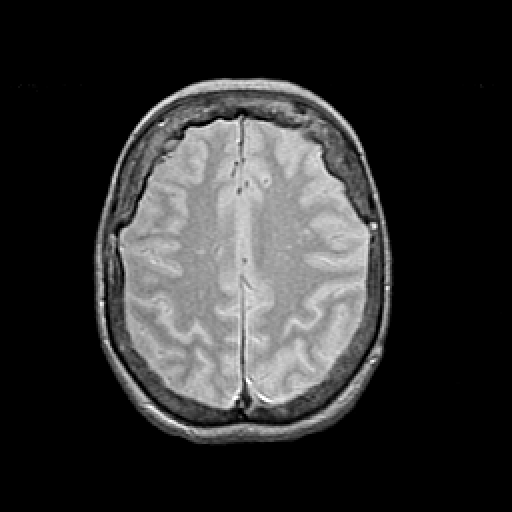

Proton density-weighted structural MR: Slice 38

Slice 38